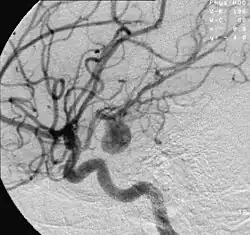

![]() | |

Angiography of an aneurysm in a brain artery. The aneurysm is the large bulge in the center of the image. | |

An aneurysm is an outward bulging, likened to a bubble or balloon, caused by a localized, abnormal, weak spot on a blood vessel wall.[1] Aneurysms may be a result of a hereditary condition or an acquired disease. Aneurysms can also be a nidus (starting point) for clot formation (thrombosis) and embolization. As an aneurysm increases in size, the risk of rupture increases, which could lead to uncontrolled bleeding.[2] Although they may occur in any blood vessel, particularly lethal examples include aneurysms of the circle of Willis in the brain, aortic aneurysms affecting the thoracic aorta, and abdominal aortic aneurysms. Aneurysms can arise in the heart itself following a heart attack, including both ventricular and atrial septal aneurysms. There are congenital atrial septal aneurysms, a rare heart defect.